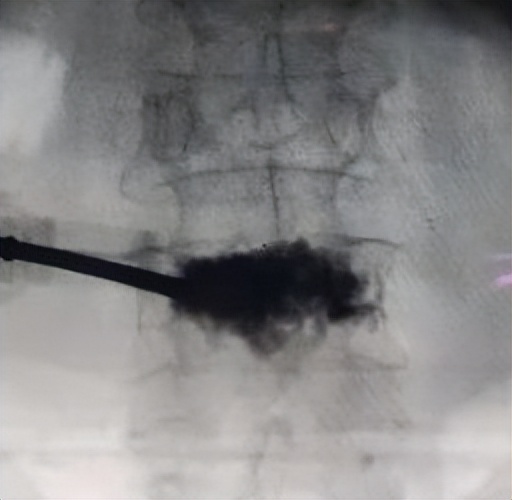

钻取通道